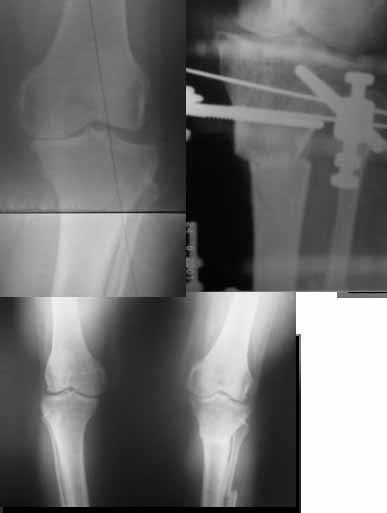

I do upper tibial osteotomies with either an ilizarov fixator and acute correction of the deformity or with an orthofix with gradual correction.

You can do the osteotomy in a "focal dome" or in a transverse fashion. The dome has the advantage of having a good contact, allowing weight bearing as tolerated early on.

Since the center of rotation of these deformities is usually near the knee joint line, lateral translation of the distal fragment is necessary to normalise all the axes.

When I use an orthofix fixator, the osteotomy is oblique, starting below the tuberosity and ending 1 cm away from the lateral cortex at the level of the head of the fibula. No fibular osteotomy is needed there. The deformity is gradually corrected over 2 or three weeks.